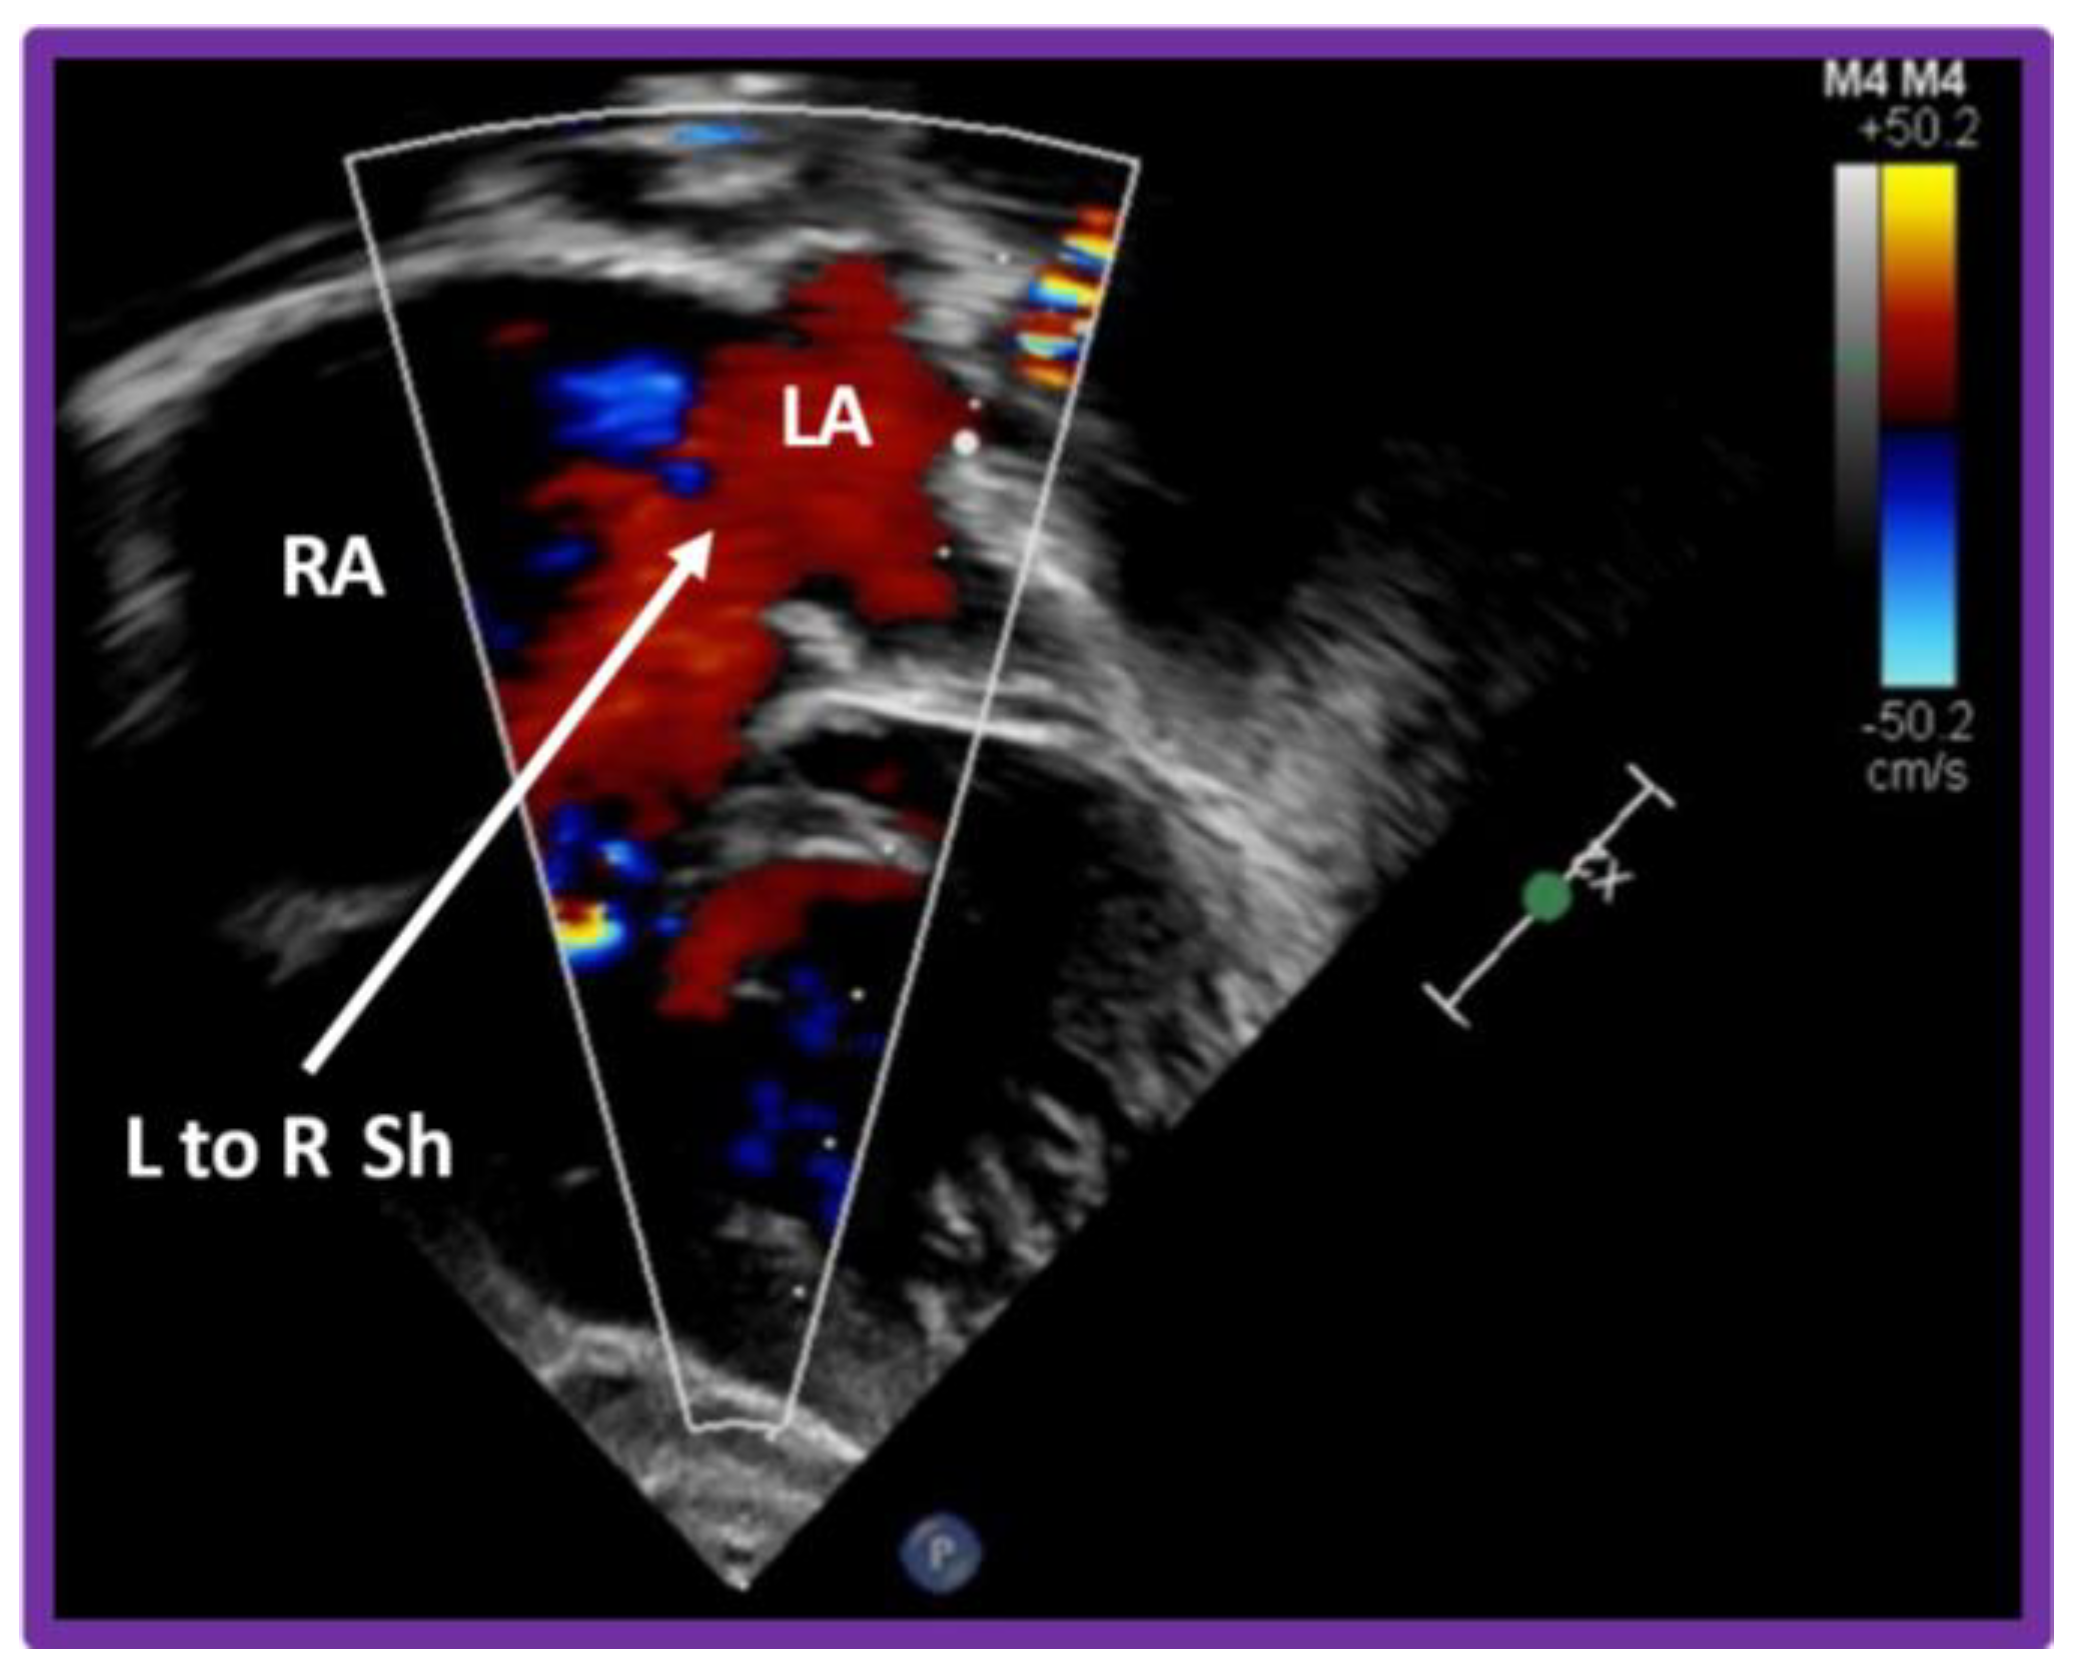

8. Echocardiogram